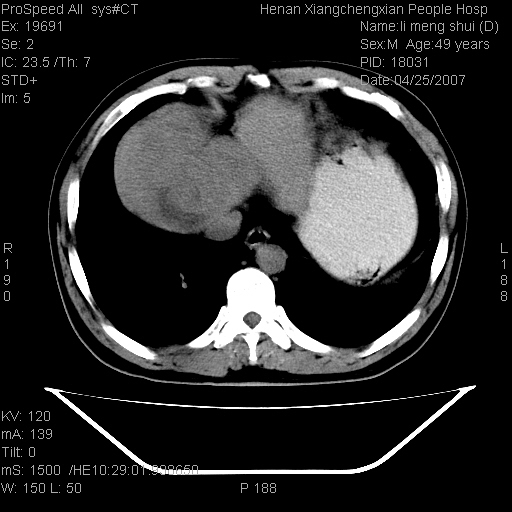

| 患者,男,49岁, 腹疼伴恶心\\呕吐20天,20天前无明显诱因出现右上腹部疼痛,钝疼,无放射,伴恶心\\呕吐,不伴发热.患者不愿增强. b超:肝脏右叶实性占位. ct:肝脏右叶可见一巨块状圆形低密度影,大小约93mm*84mm,其内可见点状高密度影,胆囊、胰腺、脾脏大小、形态及密度未见异常,腹膜后间隙未见肿大淋巴结影。 印象:肝脏右叶巨大肿块,性质待定,建议增强并穿刺活检进一步确诊。 ct平扫: ![]() ![]() ![]() ![]() ![]() ![]() ![]() ![]() ![]() ![]() ![]() ![]() ![]() ![]() ![]() ![]() ![]() 肝脏右叶肿块ct引导下穿刺活检术 患者于16时05分仰卧于ct检查台上,首先行肝脏ct扫描确定进针位置、深度、角度。在局麻下行ct引导下肝脏右叶肿块穿刺活检术。常规消毒、铺巾、局麻。在ct引导下使活检针经右侧腋中线、第9肋间隙垂直胸壁进针90mm,针头进入病变预定位置。在病变预定位置多点、多方向抽取小米样病变组织多块,涂片五张送病理检查。术后穿刺点局部无出血,未出现腹腔积液等并发症。术中及术后患者生命体征稳定,手术于17时10分成功完成。患者安返病房。 穿刺片 ![]() ![]() ![]() ![]() ![]() ![]() ![]() ![]() ![]() ![]() ![]() ![]() ![]() ![]() ![]() ![]() 病理结果肝细胞癌 ![]() 原贴地址:http://www.radinet.com.cn/forum_view.asp?forum_id=4&view_id=24130 ok |